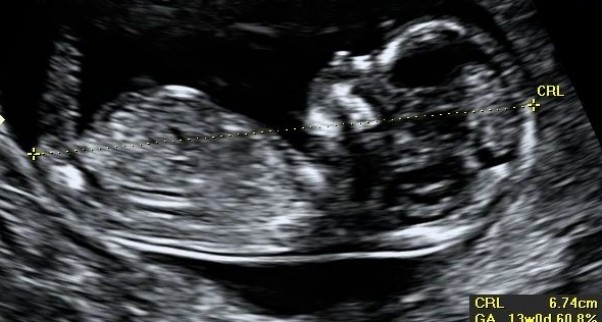

dzisiaj mieliśmy USG takie jakieś długie i bardzo dokładne. W pierwszej chwili nawet się przestraszyłem bo myślałem że coś nie tak jest bo patrzyła pani doktor i patrzyła w ten monitor, mierzyła i zaznaczała ale kiedy przemówiła ulżyło mi....okazało się że to badanie jest tak zwane parenteralne czyli musiała zmierzyć naszego Bobaska dokładnie...jakaś tam coś ..karkowa długoś wszystkie obwody przepływy krwi...wszystko jest dobrze...chciałem wiedzieć co żona pod serduchem nosi ale  ona nie chciała i nadal żyję w nieuświadomieniu :( na następnej wizycie umówię się z doktorką aby mi pokazała po kryjomu czy syn czy córka... :D mamy 13 tygodni....